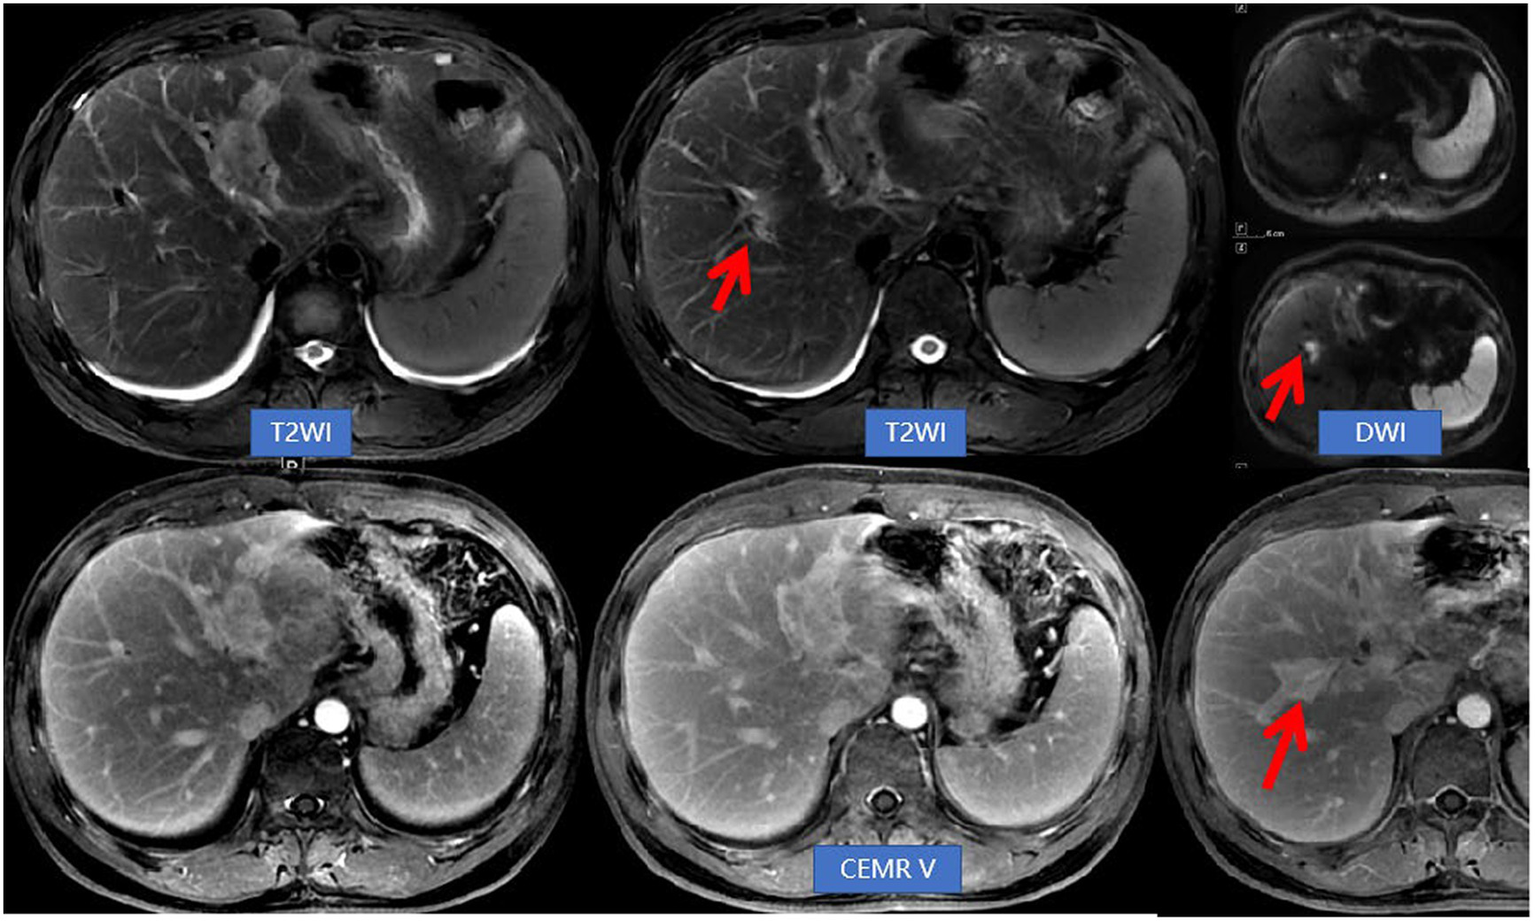

The patient was discharged from the hospital after experiencing an improvement in symptoms. A month later, he returned for routine blood tests and repeat MRI examination of the upper abdomen. The eosinophil percentage was found to be elevated, measured at 19.20%. While the original biliary duct lesions had decreased in size, new lesions with a migratory sign were observed on the upper abdominal MRI (Figure 3). The medical team suggested diagnostic glucocorticosteroid pulse therapy or needle biopsy, but the patient declined these options and instead opted for a laparoscopic left-lateral hepatic lobectomy. The postoperative pathological examination confirmed the diagnosis of EC (Figure 4). The AEC level was measured at 0.28 × 109/L 1 month post-operation and subsequently decreased to 0.09 × 109/L after 1 year.

Figure 3

Abdominal NEMR and CEMR revealed a reduction in lesions within the left hepatic lobe and hepatic hilum compared to previous findings. Additionally, there was an improvement in bile duct dilatation, while a new lesion (indicated by arrows) near the right hepatic duct was observed. This imaging feature was referred to as migratory sign.